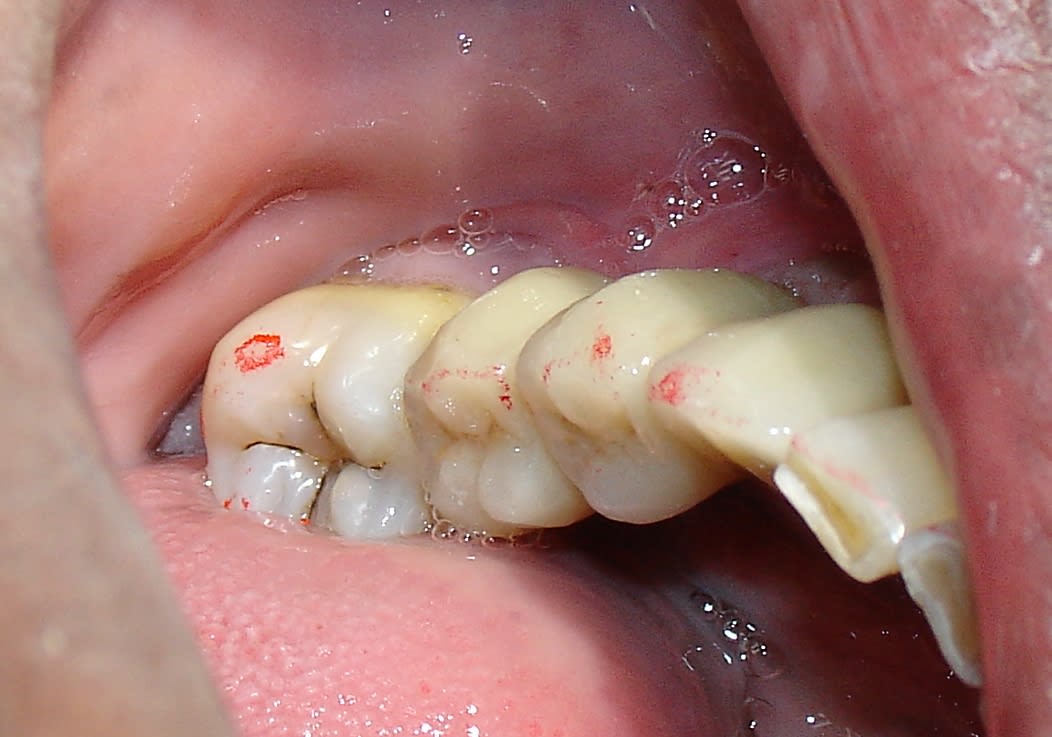

C'est fait ma première prothèse sur implant via la Medit est posé.

Merci Création Dentaire c'est rentré tout seul et en one shot. Occlusion comme les points de contact tout est nickel sur une base instable pour une réalisation conventionnelle.

Le cas n'est pas très photogénique mais bon ce n'est pas le sujet.